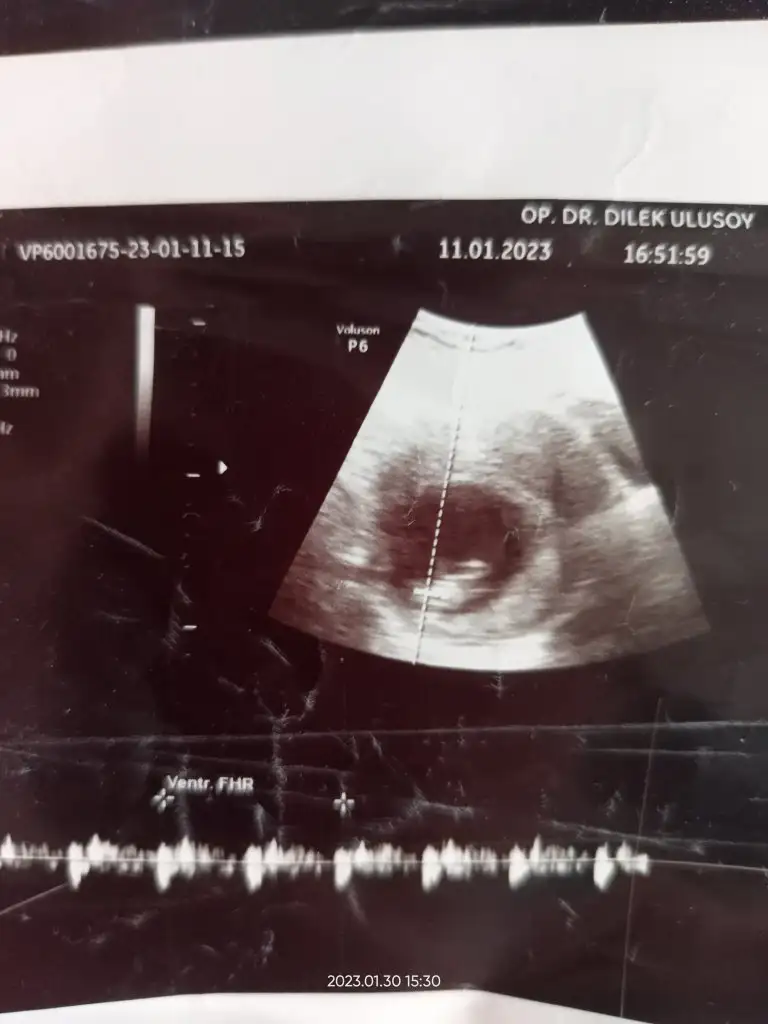

Merhaba 11e 4 haftalık cinsiyeti nedir yorumunuzu bekliyorum.

Bize de yorum yapar mısın teyzesi :) Karından ultrason